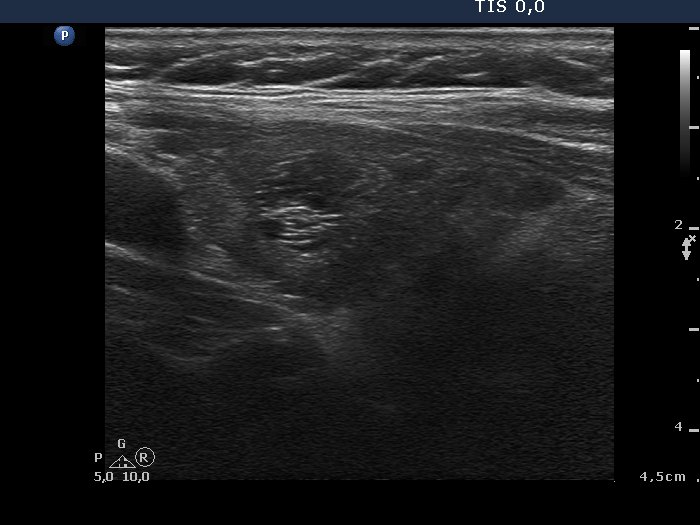

Left lobe, longitudinal scan. On the hypoechogenic pattern of the lobe, we can conclude that the cause for hyperthyroidism is very likely autoimmune thyroid disease.